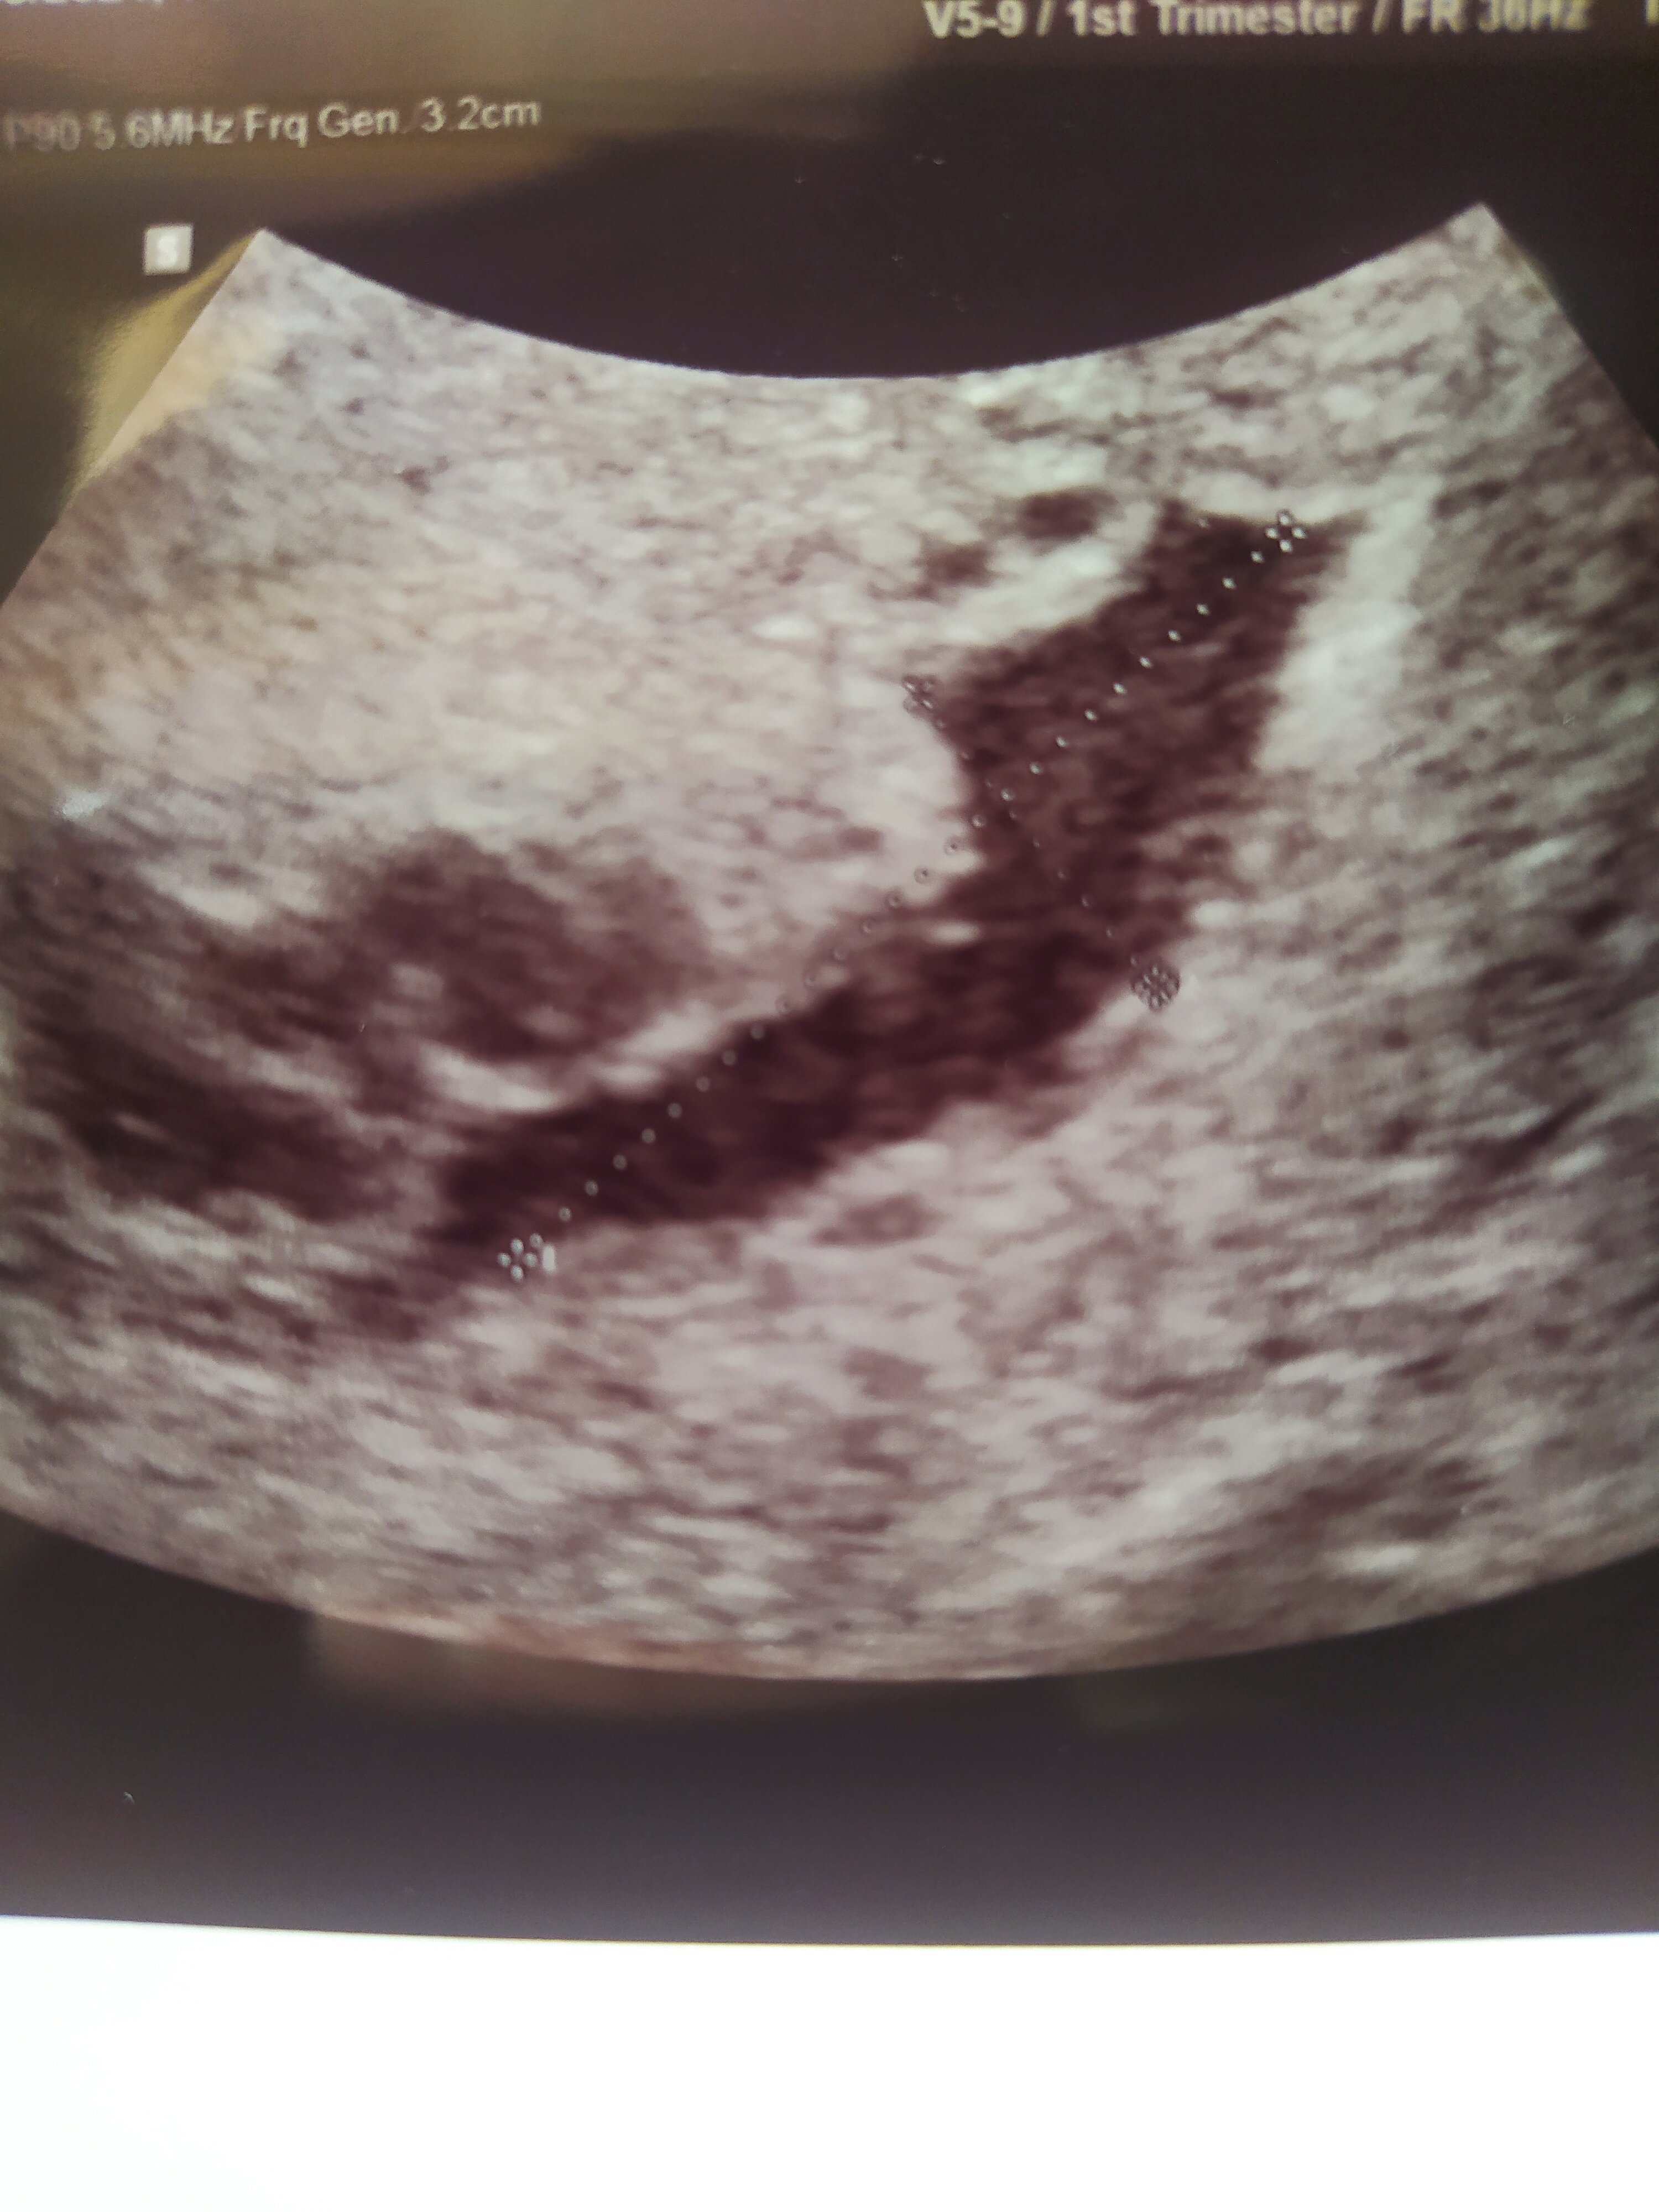

Krwiak w 7 tygodniu

Hej, byłam wczoraj na wizycie 7+1 okazało się że mam krwiaka 25x9. Dostałam Duphaston 3x1. Mówiła tylko że mam unikać biegania, skakania, jazdy na rowerze itp. Pytała jaki mam charakter pracy czy nie chcę zwolnienia. Zaczynam się denerwować, bo w pracy niby siedzę przy biurku ale często też wstaje schylam się, biorę (nie ciężkie, ok 2kg) rzeczy. Mam nadzieję że taka "aktywność" mi nie zaszkodzi. Możecie podzielić się swoimi doświadczeniami jeśli miałyście krwiaka?

Zdjęcie krwiaka, zarodek jest dalej na lewo, nie widać go na zdjęciu.